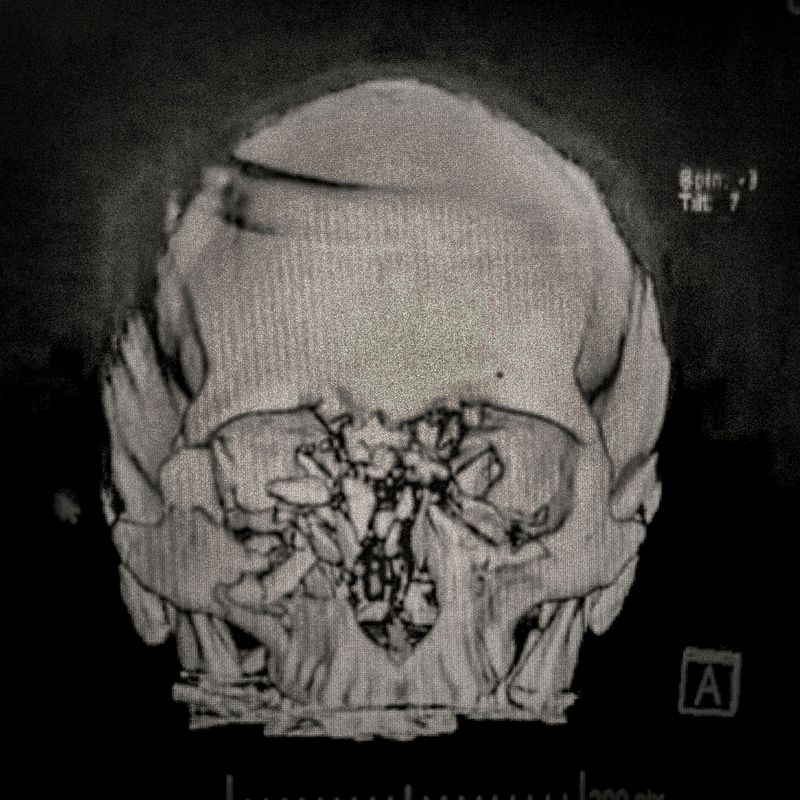

X-ray showing the pellet embedded in the skull of Ybar Soto (29) Ybar was hit by a pellet that lodged in his right eye on October 24, 2019 in Plaza Italia. Santiago. His diagnosis was ocular burst. Santiago, Chile. December 28, 2019